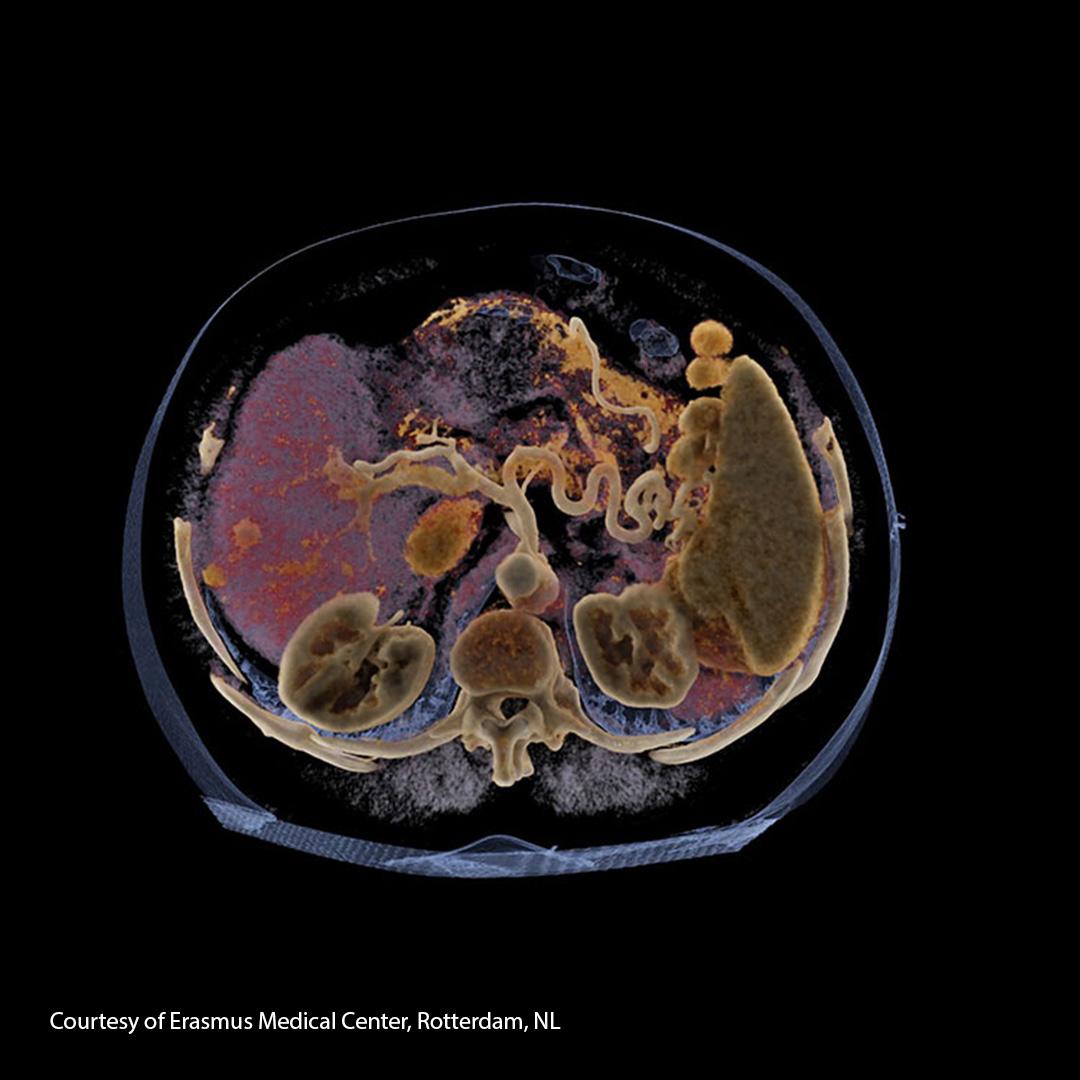

In order to accurately represent a patient´s liver, a lot of data is required for its digital twin.

Modeling the human liverI think it’s very rewarding to try and apply science to build solutions that could help patients live longer and healthier lives.

Chloé Audigier, Senior AI Research Scientist at Siemens Healthineers

- The concepts and information presented here are based on research results that are not commercially available. Further commercial availability cannot be guaranteed.